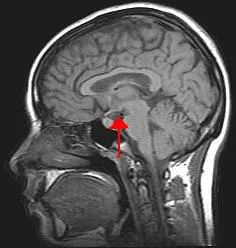

As I explain how the brain works, I invite you to look at illustrations to get a visual understanding of what I'm talking about. Here is an X-ray image cross-section of the brain.

In this image the skull is white. The darker area just below the skull is occupied by cerebrospinal fluid, the brain's shock absorber. The sketchy white line inside that marks the dura mater, a tough fibrous covering over the brain. Going deeper, more fluid cushions the brain, and then you see the convoluted layer, the cortex (Latin for "bark" or "rind"), where we do our thinking. The mushroom-like whitish cap at the brain's center is the corpus callosum, containing the great nerve tracts that connect the left and right sides of the cortex. The red arrow in this photo points at the pituitary gland and hypothalamus, that evolutionarily older part of the brain that governs blood pressure, temperature, wakefulness, and most of our other housekeeping functions. The "mushroom stalk" in the center of the skull and to the right of the arrow is the midbrain, which functions something like a main telephone switching office and connects to the spinal cord. The smaller convoluted part to the right of the midbrain is the cerebellum, which coordinates our muscles as we walk, swim, and dance ballet. The area between the "mushroom cap" and the "mushroom stalk" includes the limbic system where we experience emotion.